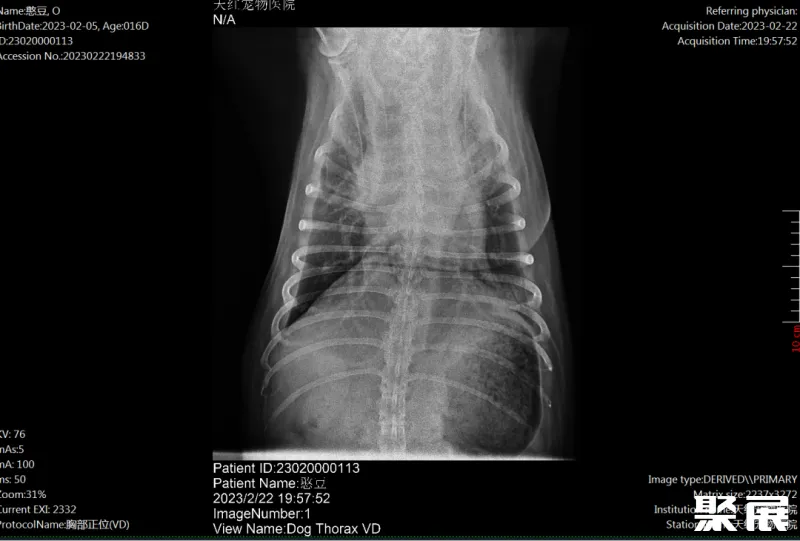

1.1 基础信息姓名:憨豆,性别:公,品种:松狮,年龄:12岁,体重:40kg。平时饮食:狗粮为主,鸡胸肉一周2次。独居,疫苗卫佳捌免疫完整,驱虫记录完整。2月5号在家呕吐一次,呼吸急促,带到分院就诊,检查提示CRP偏高,随后转到我院就诊。体格检查体温40.5℃,呼吸频率45次/min,心率112次/min,尿失禁,尿检提示细菌感染,X光提示气管狭窄,肺部感染,血检可见贫血,存在明显炎症感染。

综上检查,血常规提示存在贫血,白细胞与CRP上升提示机体存在明显炎症感染。生化与CPL结果未见明显异常。血气同时提示贫血,膀胱穿刺取尿进行尿沉渣检查在大量红细胞与炎性细胞背景下可见大量杆菌增殖,X-RAY提示肺部明显感染。 结合主诉该病例诊断为肺炎与细菌性膀胱炎。

一周后复查,肺部不透明度明显降低。